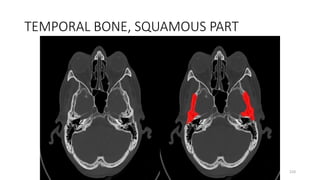

• Foramen magnum

43